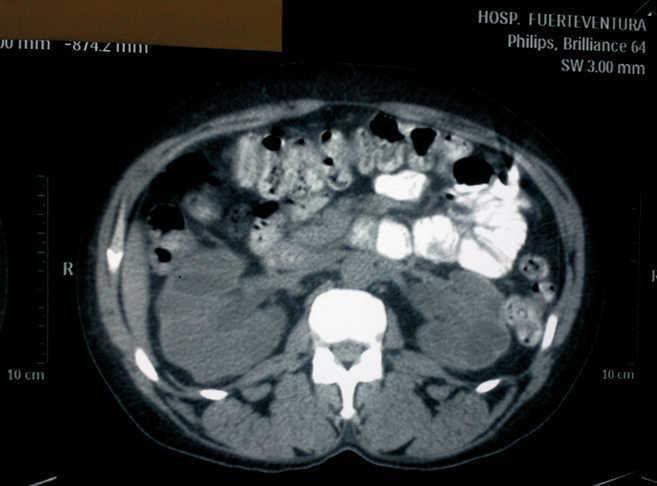

We present the case of a female patient, 41 years of age, with no significant past medical history, who was sent from the emergency department due to deterioration of renal function with serum creatinine (SCr) of 6.5mg/dl, in the setting of vaginal bleeding requiring transfusions. At that time, she was diagnosed with uterine fibroids by the gynaecology service. She was admitted for further work-up and a renal ultrasound was performed, showing grade IV bilateral hydronephrosis, with poor corticomedullary differentiation, but without visible ureters, for which a CT scan was performed. The CT showed grade IV bilateral ureterohydronephrosis secondary to extrinsic compression by the myomatous uterus, which measured 13 x 9cm (Figures 1 and 2). The urology service was notified, which placed a double “J” catheter in the right ureter, but was unable to place one in the left ureter. Evaluation by the gynaecology service was requested, which postponed a simple hysterectomy to the following week.

Figure 2. Lower CT cut where bilateral ureteral dilatation can be seen.